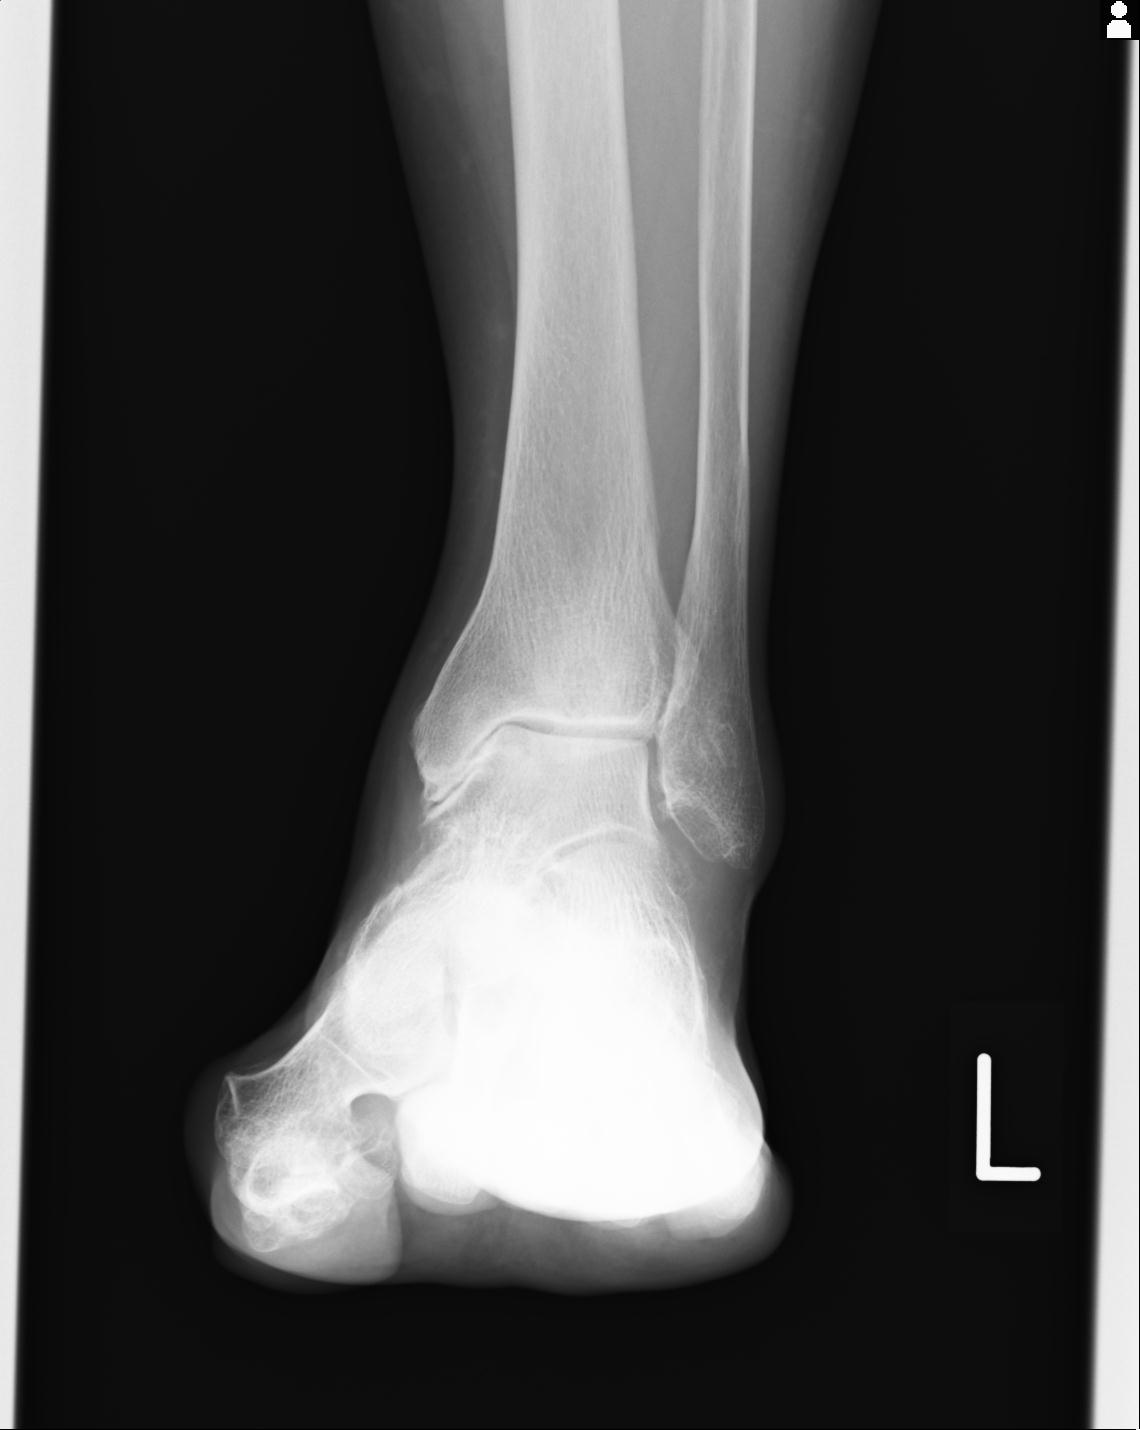

102755 1/4 2R 1/15 2R 右足関節 68歳女性 右三果脱臼骨折